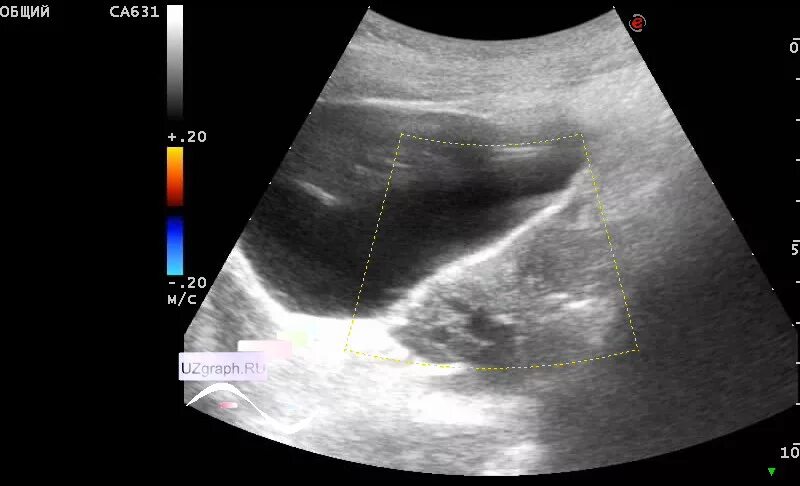

Апоплексия яичника после операции